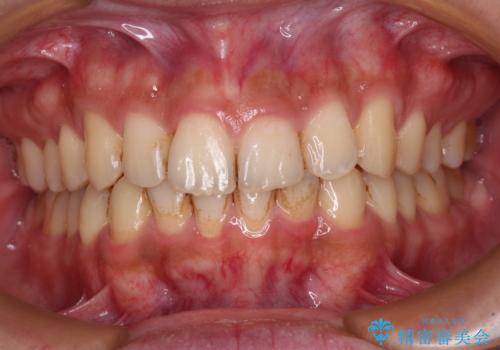

前歯のデコボコをスッキリ改善 インビザライン矯正

- 上下前歯のデコボコを気にして来院された患者様です。

全体的に叢生は軽度であったため、インビザラインにて矯正治療を行うこととしました。

デコボコの改善はもちろん、下顎前歯が隠れてしまうディープバイトも一緒に改善することができ、奥歯への負担を軽減することができました。